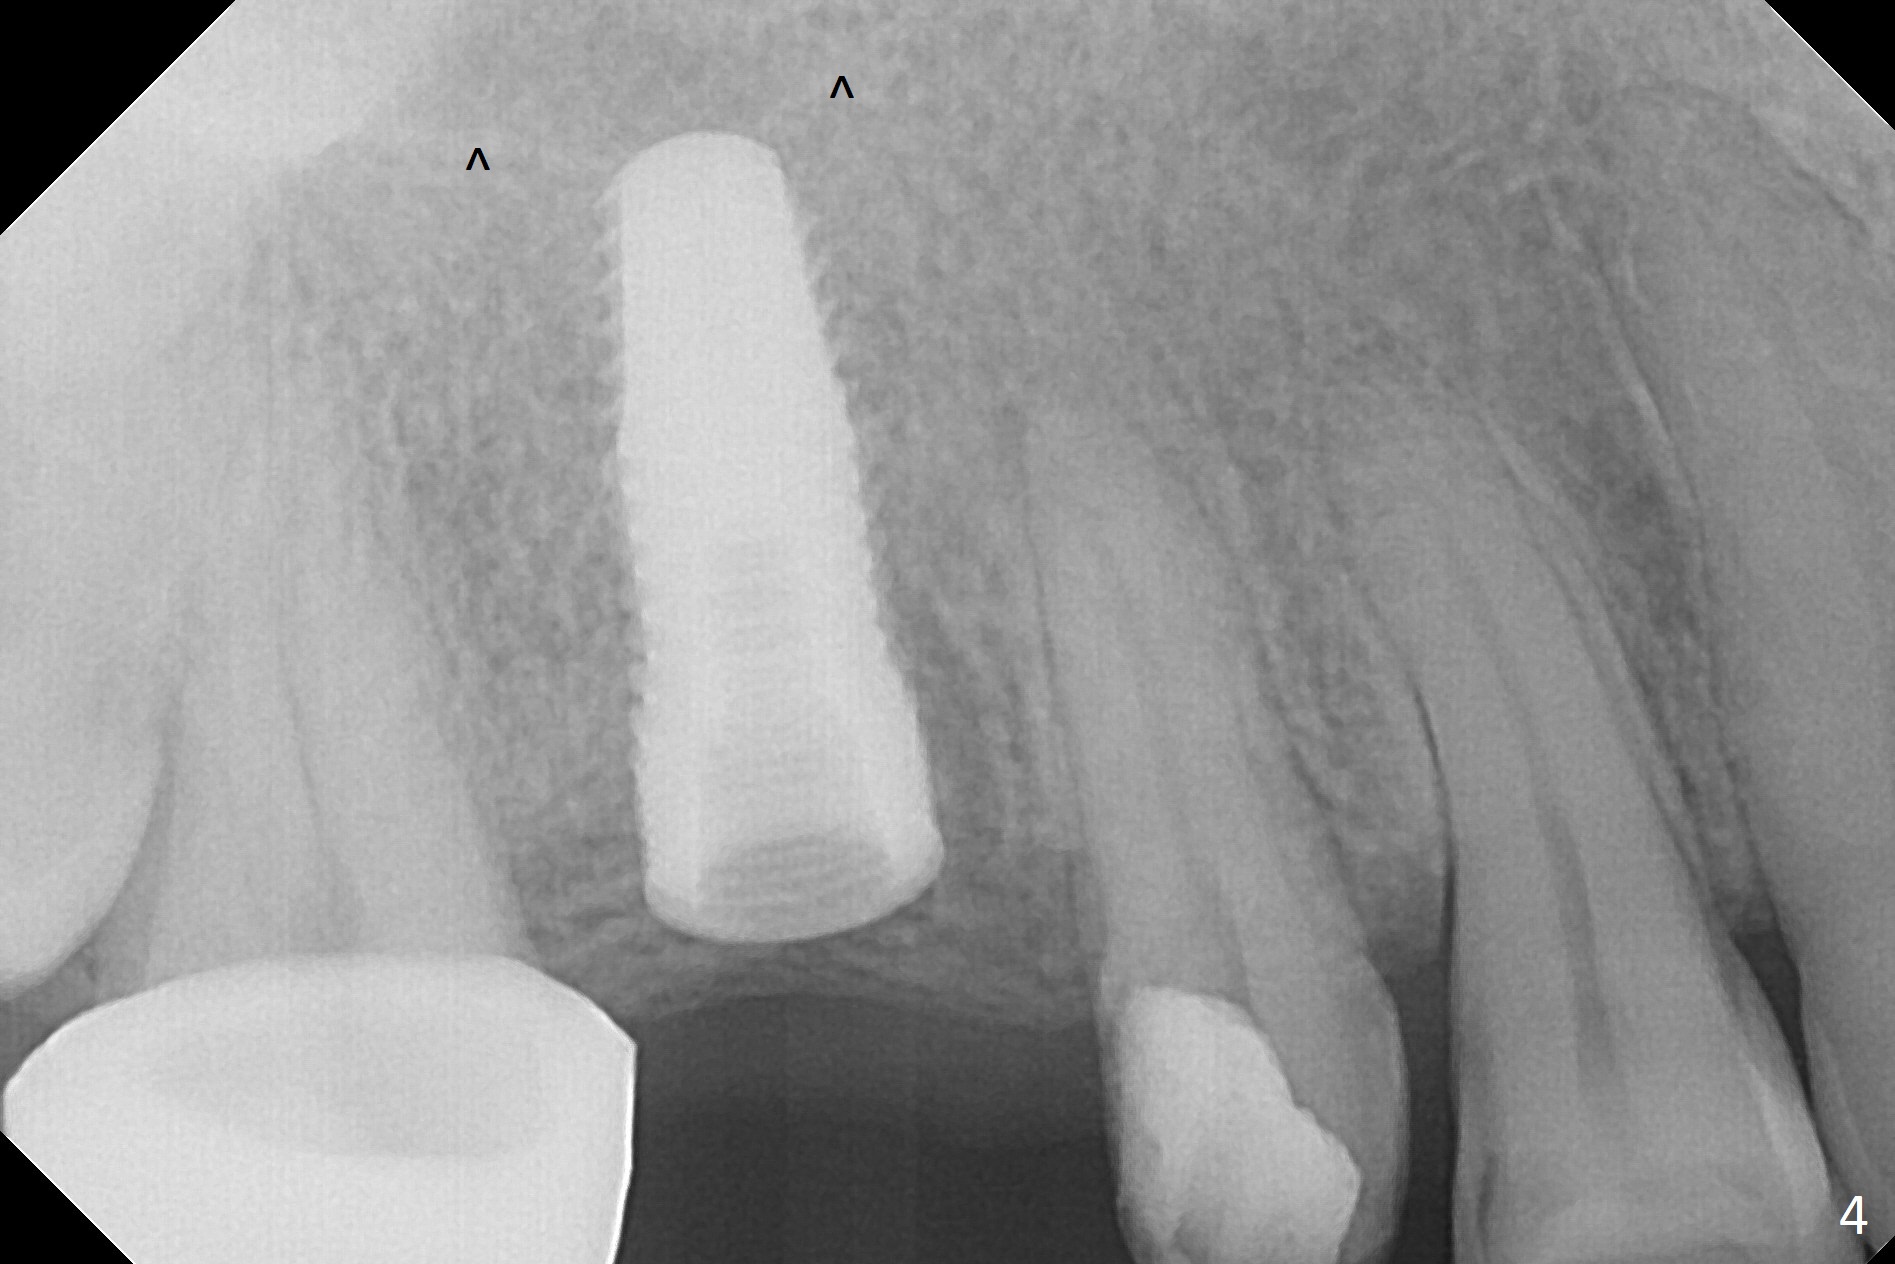

When the bridge is partially removed, the tooth #4 is found to have extensive caries. IRM is placed following carious removal (Fig.1). Magic Split testing shows that the bone density is high (flapless). Osteotomy is initiated by 1.6 mm drill, but the handle of the drill needs to shift mesial (Fig.1 red arrow). When the latter is done, the whole drill (2 mm) needs to move distal (Fig.2 double red arrows). When a 4.5x14 mm drill finishes the osteotomy, it is in the middle of the edentulous space (Fig.3). After use of 5 mm tap, a 5.3x14 mm implant cannot reach the depth (Fig.4,5). Following increase in osteotomy depth from 16 to 18 mm (gingival margin) until 5 mm drill in diameter, the implant placement level is more ideal (Fig.6,7, slightly subcrestal) with insertion torque maintaining at >55 Ncm. The sinus floor (Fig.4 arrowheads) may be penetrated when the osteotomy depth increases (Fig.7 *), but the sinus membrane remains intact.